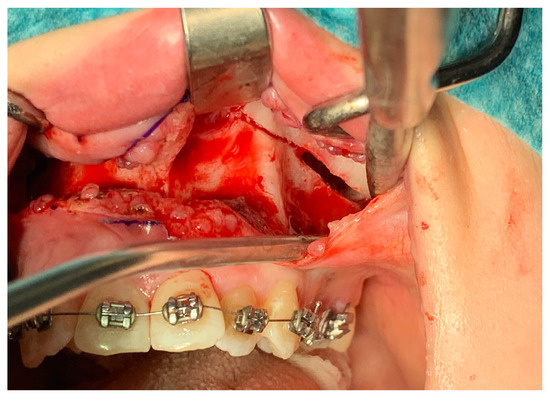

2.2. Protocol of Surgical Treatment and Postoperative Examinations

| Palatal mucosal necrosis—2 cases | Bone loss/lack of adhesion in the distraction gap—5 cases |

| Perforation of the maxillary alveolar process caused by the distractor—1 case | Maxillary incisor necrosis—2 cases |